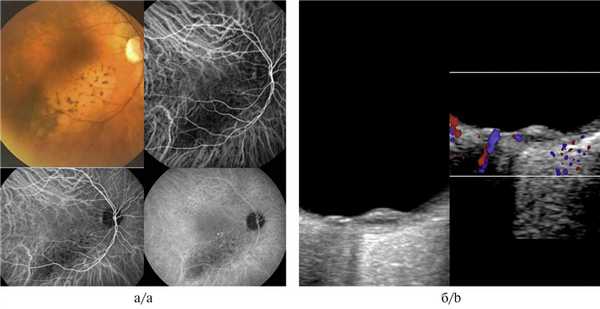

Офтальмоскопия: OD — в центральной зоне глазного дна единичные мелкие просовидные очажки округлой формы. На периферии очаговой патологии не выявлено (рис. 1, а). Рисунок 1. Офтальмоскопия друз (а) и проминирующего очага (б). Здесь и на рис. 4, а, б: желтой стрелкой указана зона глазного дна, на уровне которой проведен томографический срез методом СОКТ.

OS — в макулярной зоне в 1,5 pupilla diametr (PD) от диска зрительного нерва по меридианам с 14 до 16 ч определялся проминирующий желтый беспигментный очаг с гладкой поверхностью, нечеткими неровными границами, размером 2×2 PD (см. рис. 1, б).

Для уточненной дифференциальной диагностики проведены флюоресцентная ангиография и спектральная оптическая когерентная томография.

Флюоресцентная ангиография: OD в венозную фазу — несколько мелких гиперфлюоресцирующих округлых фокусов (друзы).

OS — в макулярной зоне выраженная гипофлюоресценция очага с четкими границами, окруженная обширной зоной гиперфлюоресценции (отслойка нейроэпителия — НЭ). В парамакулярных зонах — очаги гипофлюоресценции (микроотслойки ретинального пигментного эпителия — РПЭ) и множественные мелкие гиперфлюоресцирующие округлые очаги (сливные друзы) (рис. 2). Рисунок 2. Флюоресцентная ангиография поздней стадии возрастной макулярной дегенерации, проявляющейся проминирующим очагом (объяснения в тексте).

Спектральная оптическая когерентная томография: OD — в макулярной зоне множественные отслойки РПЭ (рис. 3, а). Рисунок 3. СОКТ друз (а) и поздней стадии возрастной макулярной дегенерации, проявляющейся проминирующим очагом (б). Красная стрелка — отслойка РПЭ; синяя стрелка — отслойка НЭ; зеленая стрелка — ровный профиль мембраны Бруха (объяснения в тексте).

OS — в макулярной зоне высокая волнообразная отслойка РПЭ с отслойкой НЭ в сопредельных зонах, ровный профиль мембраны Бруха (см. рис. 3, б).

На основании совокупности результатов проведенных исследований диагностирована бинокулярная возрастная макулярная дегенерация (ранняя стадия — OD, поздняя стадия — OS).

Приведенные два клинических случая интересны тем, что оба пациента имеют онкологический анамнез и у обоих на глазном дне офтальмоскопически выявлен желтый проминирующий очаг в постэкваториальной зоне, что может указывать на метастатический характер поражения глаза. Однако при тщательном обследовании с использованием методов флюоресцентной ангиографии и спектральной оптической когерентной томографии по совокупности томографических и ангиографических симптомов в одном случае диагноз метастаза снят, а в другом подтвержден.

В первом случае гипофлюоресценция в зоне очага с гиперфлюоресценцией по его периферии в совокупности с томографически выявленной отслойкой РПЭ и сохранением ровного профиля мембраны Бруха позволяют снять диагноз вторичной злокачественной опухоли хориоидеи и установить возрастную макулярную дегенерацию.